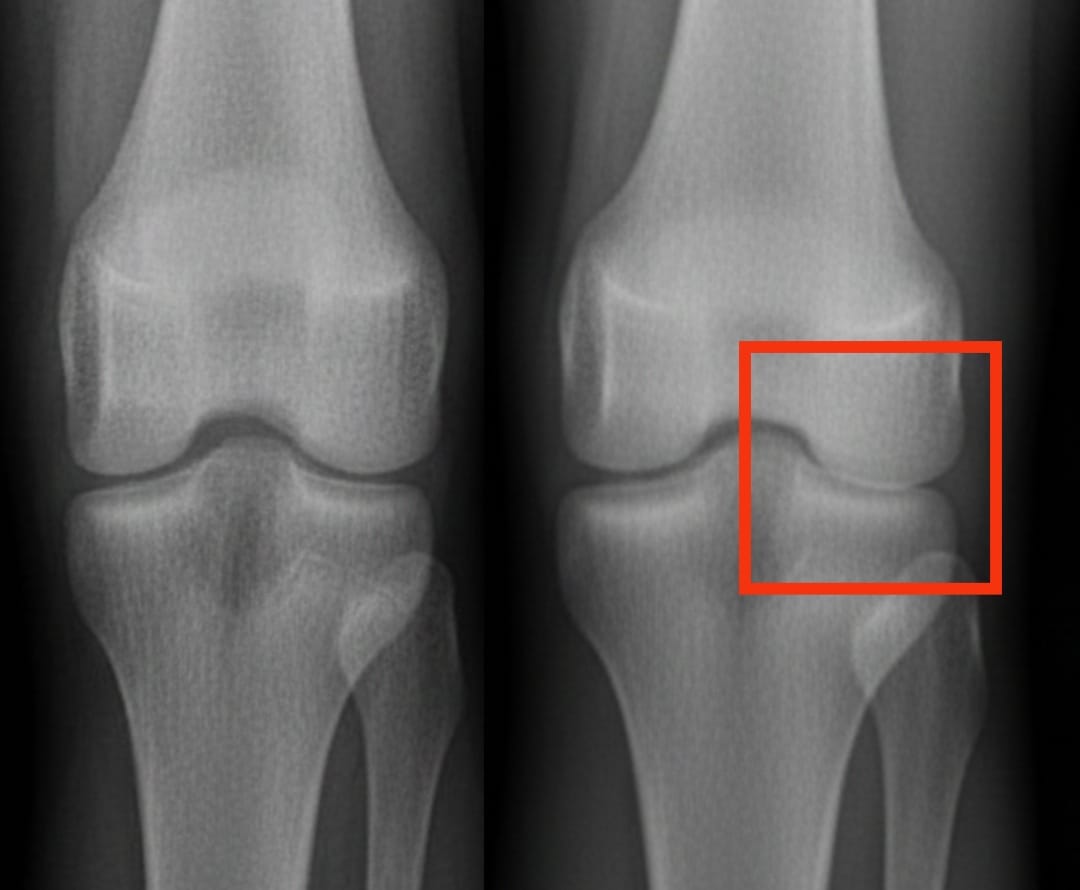

Артроз колена затрагивает сотни миллионов людей по всему миру. Он характеризуется прогрессирующим износом хряща, что приводит к боли и затруднениям в движении. Среди предлагаемых решений инъекции обогащённой тромбоцитами плазмы вызывают всё больший интерес. Это лечение использует собственную кровь пациента, концентрированную по тромбоцитам, для стимуляции восстановления тканей и уменьшения воспаления.

Недавний анализ сравнил эффективность обогащённой тромбоцитами плазмы с другими распространёнными инъекциями: гиалуроновой кислотой, кортикостероидами и физиологическим раствором плацебо. Результаты показывают, что обогащённая тромбоцитами плазма значительно улучшает боль и подвижность через шесть месяцев, а положительный эффект сохраняется до года. Эти улучшения более выражены, чем при использовании гиалуроновой кислоты или кортикостероидов, и значительно превосходят эффект плацебо.